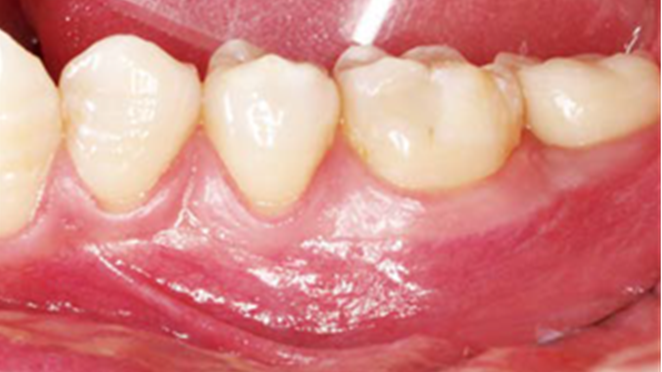

Clinical case: Single molar implant with bone augmentation

- Courtesy of Dr. Jung Sam Lee, Korea -

Keywords

AnyOne, bone augmentation, osteotomy socket, peri-implant tissue, autogenous bone, GBR, single replacement, Auto-Max, Dr. Jung Sam Lee

Products:

AnyOne implant system, Auto-Max